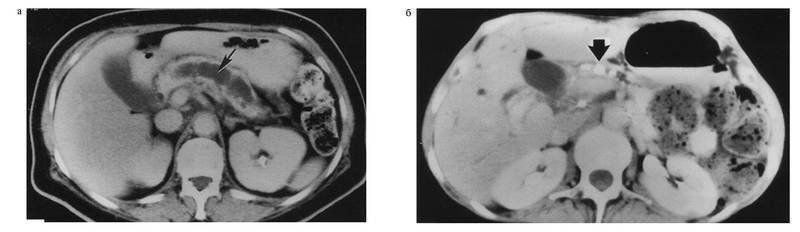

При выраженном повышении эхогснности (см. рис. 4-19 a) всей паренхимы ПЖ конкременты выявляют только по наличию «акустических теней». Линейное расположение указывает на их расположение в ГПП (см. рис. 4-19 б). Передко выявляют значительное расширение протока, дистальнее расположенных в нём конкрементов.

Рис. 4-19. Ультрасонограмма поджелудочной железы при хроническом панкреатите:

а — визуализируется диффузно-неоднородная эхоструктура поджелудочной железы с чередованием зон средней и повышенной эхоплотности, не имеющих чёткого отграничения друг от друга; б — визуализируются конкременты протоков (показано тонкими стрелками) и расширенный сегментированный панкреатический проток (показан широкими стрелками); в — визуализируются гиперэхогенные поля на фоне гипоэхогенных зон в поджелудочной железе

В трети случаев при ХП контур железы размытый, неровный, реже зазубренный, поэтому при ХП границу между ПЖ и окружающей тканью в ряде случаев определить точно нельзя. В других случаях контуры ПЖ могут быть ровными, без зазубрин, но с крупными гладкими выступами, «горбами», нарушающими в некоторой степени форму железы.

КТ предоставляет возможность установить диагноз, в первую очередь на этапе осложнений панкреатита, когда чаще всего выявляются кальцификации, псевдокисты, поражения соседних органов, атрофия паренхимы поджелудочной железы и малигнизация. Единственным надежным признаком неосложненного хронического панкреатита, который можно обнаружить с помощью этого метода, является изменение крупных протоков железы (дилатация или стеноз).

При обострении хронического панкреатита наблюдается увеличение поджелудочной железы, нечеткость контуров, инфильтрация окружающих тканей, а также неоднородная структура органа из-за участков фиброза, кальцификатов и кальцинатов в тканях и протоках поджелудочной железы (кальцифицирующий панкреатит). Для поздних стадий хронического панкреатита также характерно уменьшение размеров поджелудочной железы и расширение вирсунгова протока.